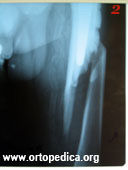

1,2. Перелом бедренной кости ниже уровня эндопротеза